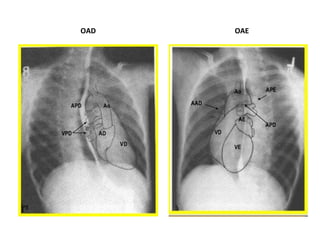

***OAE e OPD –

pulmão direito,

traquéia, caixa torácica

com o coração e aorta à

frente da coluna

vertebral.

OAE

OPE

OPD

OAD

###OAD e OPE –

pulmão esquerdo,

traquéia, caixa

torácica com o

coração e a aorta à

OAD OAE